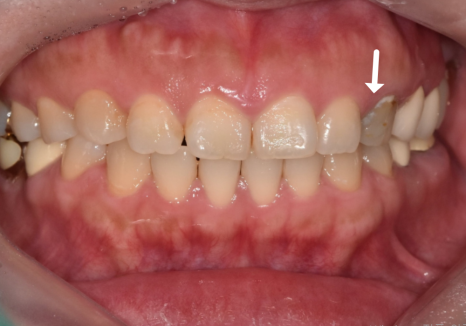

이러한 디테일한 과정을 거친 덕분에

옆 치아와 이질감 없이 밝고 자연스러운

색상으로 완성되었습니다. ^^

251101(전) 251108 (후)

다행히 이 환자분은 송곳니라

치아가 깨지기 전에

크라운 치료를 마칠 수 있었습니다.